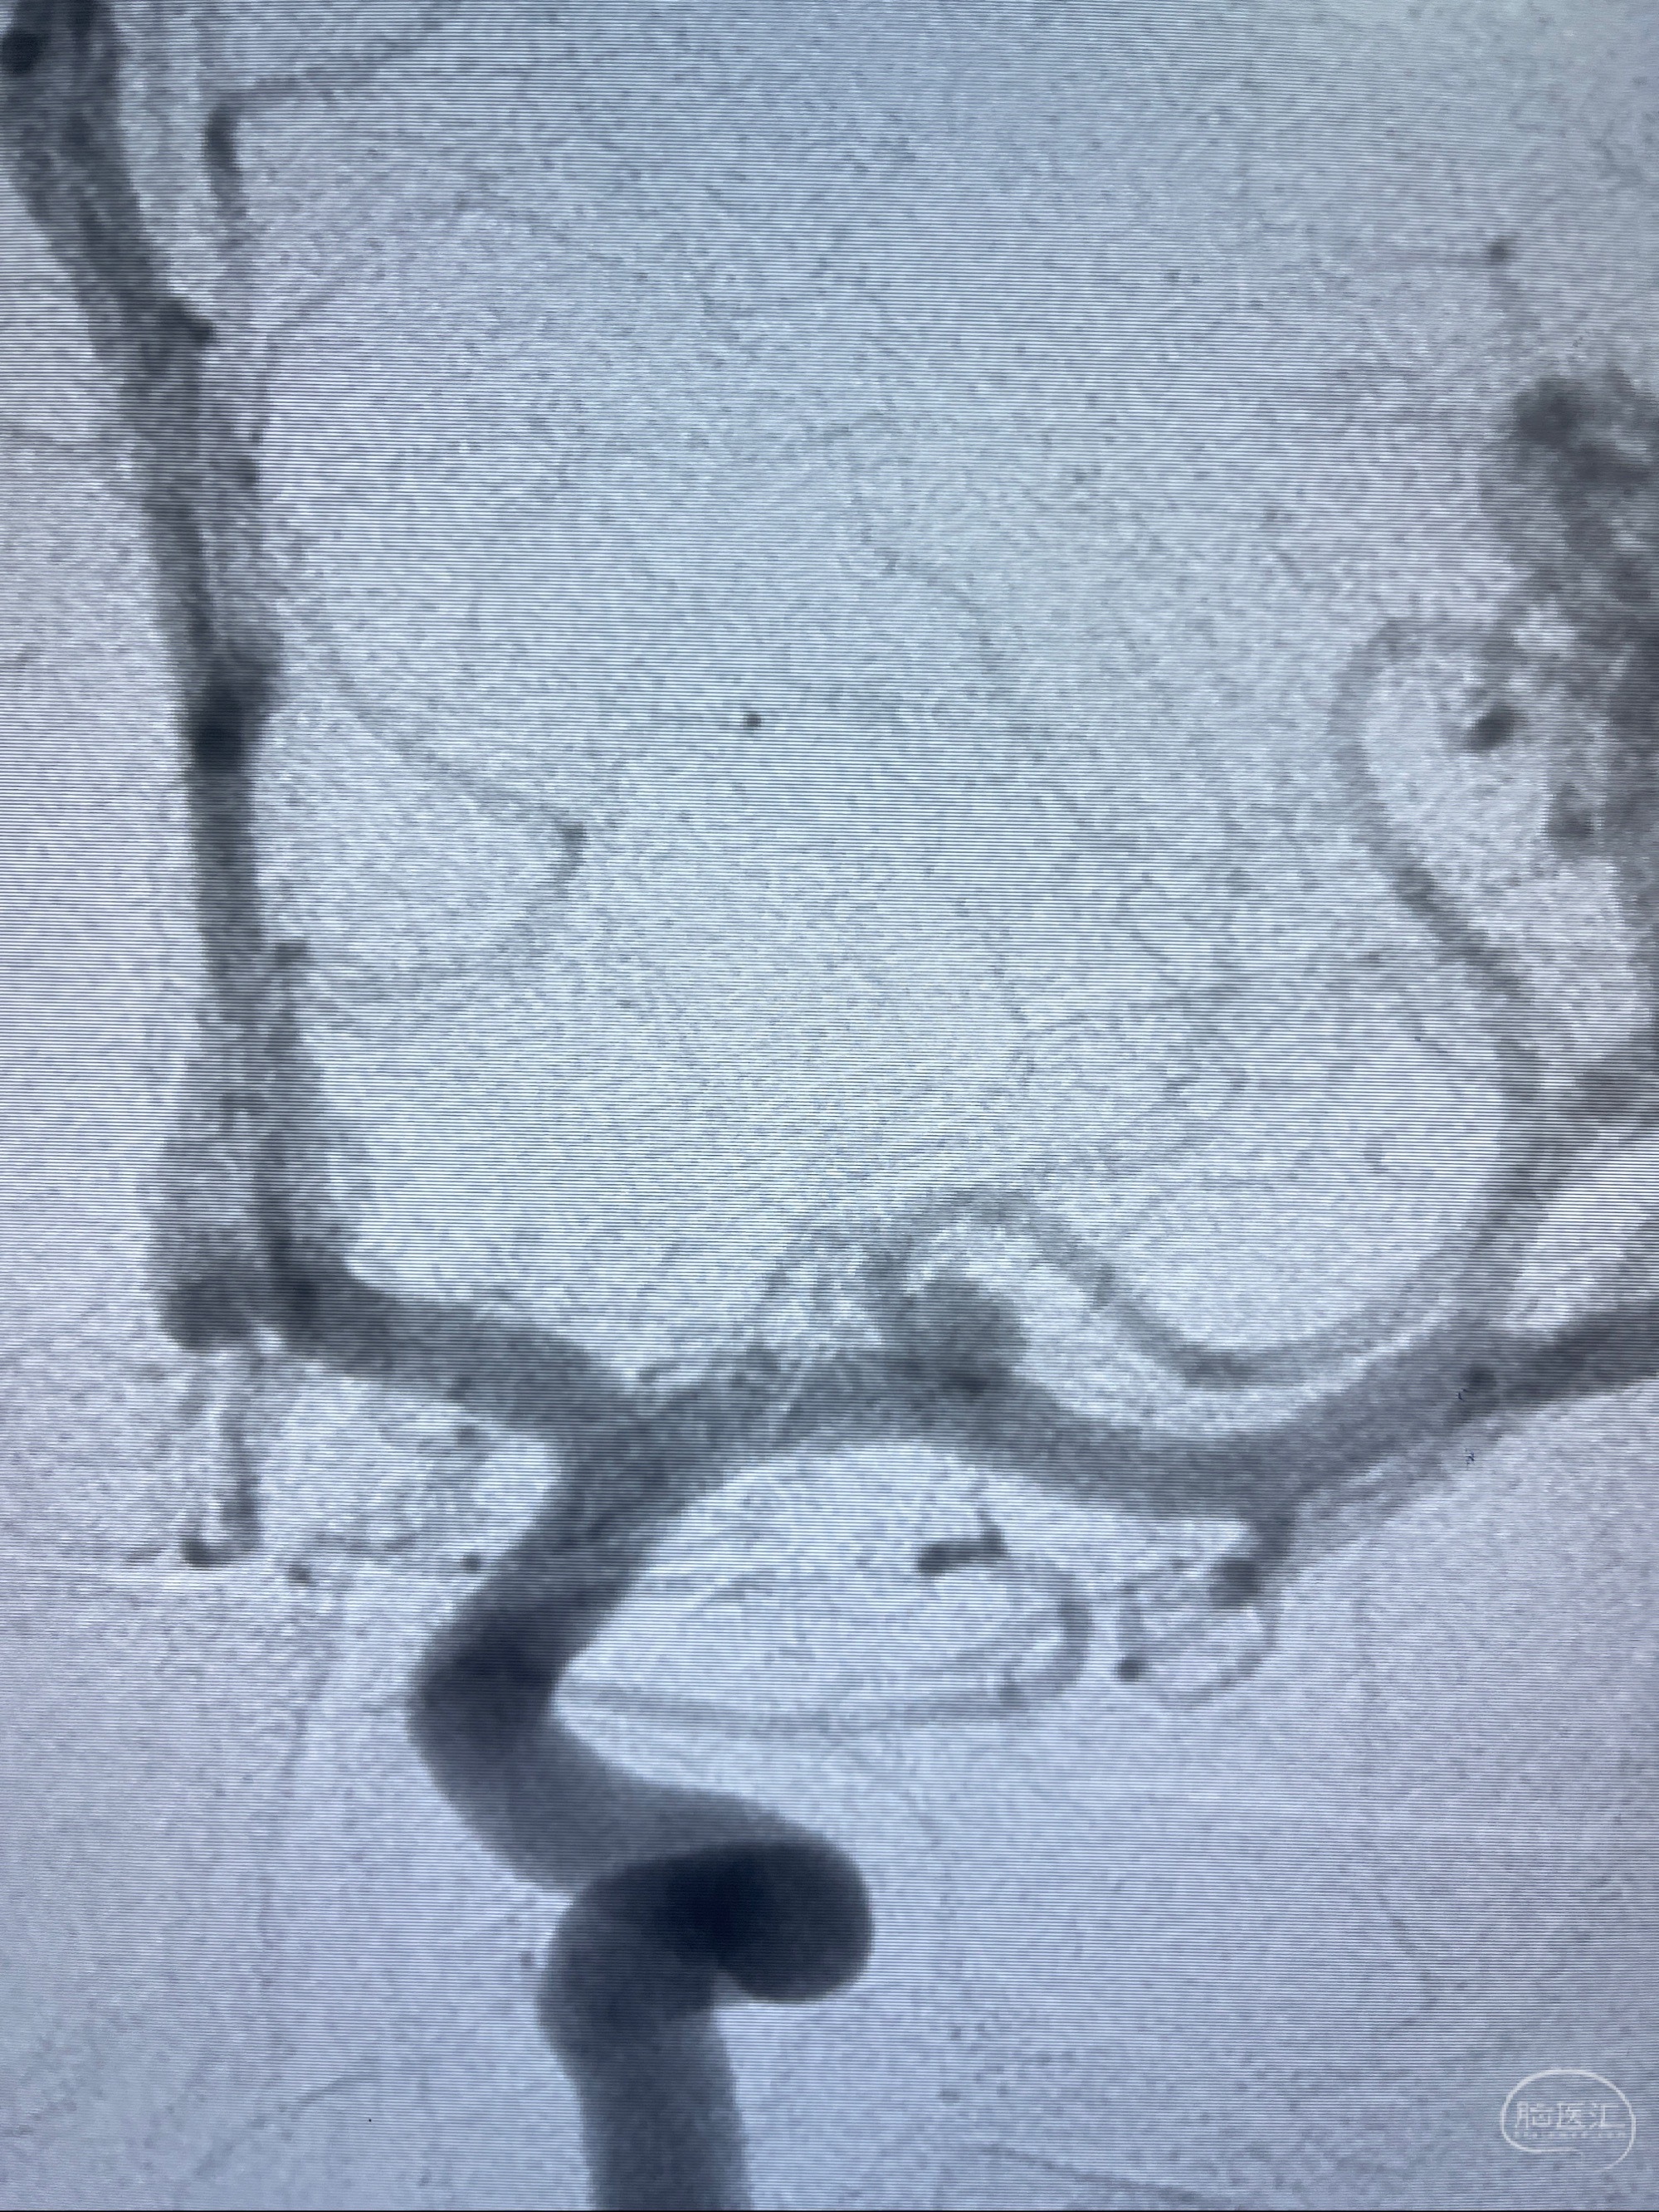

2023-08-14DSA:

左侧大脑中动脉动脉瘤,约2.6-2.8-3.4-2mm大小(瘤颈部、瘤体部、瘤高)